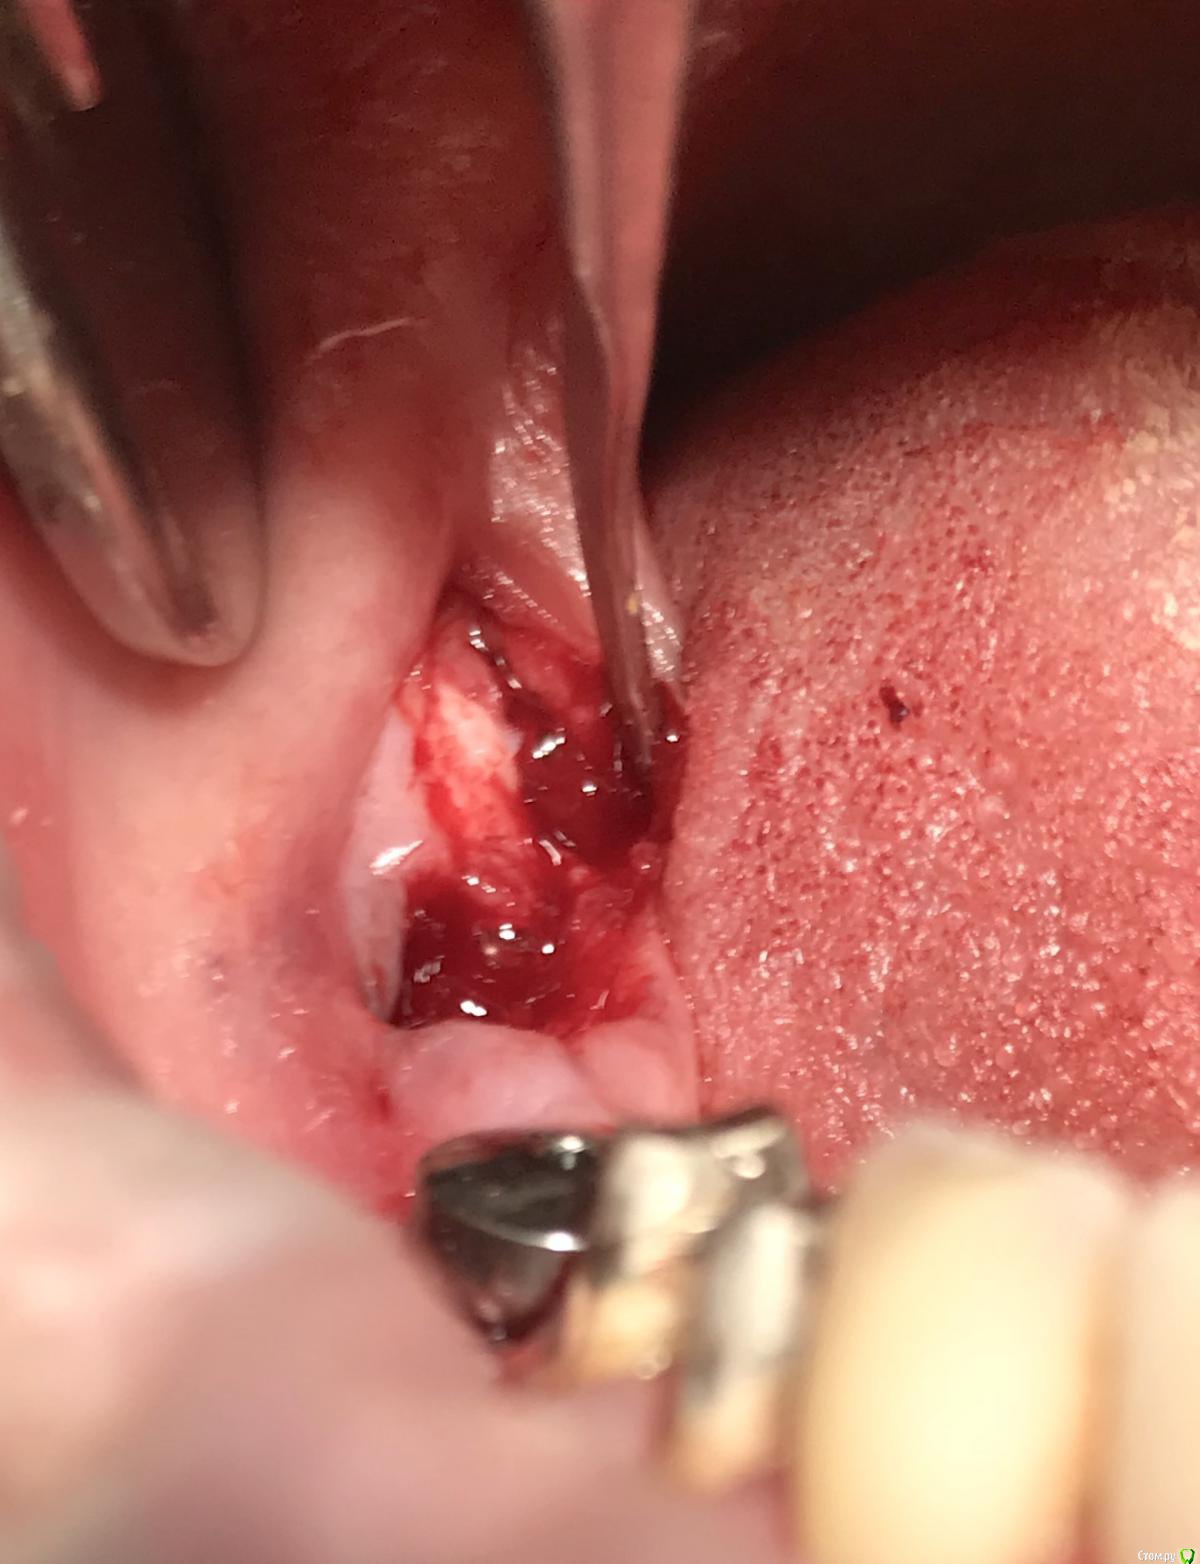

Женька Опубликовано 17 февраля, 2023 Поделиться Опубликовано 17 февраля, 2023 (изменено) И в догоночку 1.8... удаление зуба - 5 минут, удаление верхушки - 2 часа. Зуб полная ретенция, лежал близко, но прямо под пазухой, плёвое дело! отломался нёбный апекс, борьба с кровотечением, ничего не видно, отмылся - вроде видно. Ковырялочка рутпикером, вижу что корень смещается только в одном направлении-в сторону пазухи и уже прямо под границы лунки уходит от меня. В итоге ковырялся-ковырялся, пытался достать хоть как-то. В конце плюнул, распилил перегородку в лунке в глубине и сместил в лунку. А дальше чуть не потерялся апекс в мягких тканях . Но достал, главное что видно теперь всё! p.s. это таже самая пациентка) Завтра ещё скину, что-то на этой неделе прям везёт, из 3х зубов, всё три со сломанными апексами) Изменено 17 февраля, 2023 пользователем Женька 1 Ссылка на комментарий